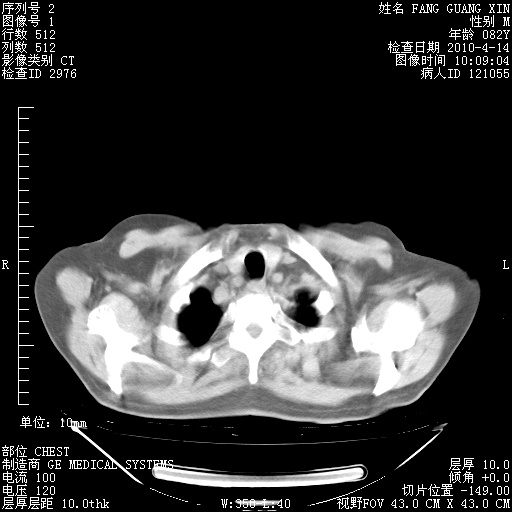

4月14日肺部CT

23.JPG

24.JPG

25.JPG

26.JPG